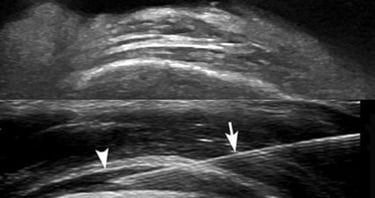

Infiltrazioni Ecoguidate

Ci sono diversi tipi di infiltrazioni.

Quando è possibile effettuarle in ecoguida il paziente ha diversi vantaggi, ad iniziare dalla precisione dell’etto e dalla consapevolezza che il medico possa scegliere la sede di iniezione più indolore possibile.